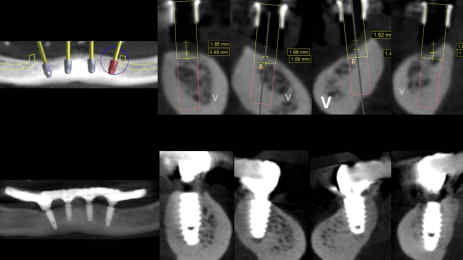

The provisional prosthesis was directly relined and secured using titanium abutments and flowable resin (Figures 9, 10). The installation of the temporary prosthesis for immediate loading was performed (Figure 11). The final panoramic radiograph and tomography image showing the result was obtained, revealing the implant placement with immediate provisional fixed rehabilitation (Figures 12, 13).

FIGURE 12: Initial software planning and the final panoramic result of implant placement with immediate provisional fixed rehabilitation

Tomograph images show the results (right)